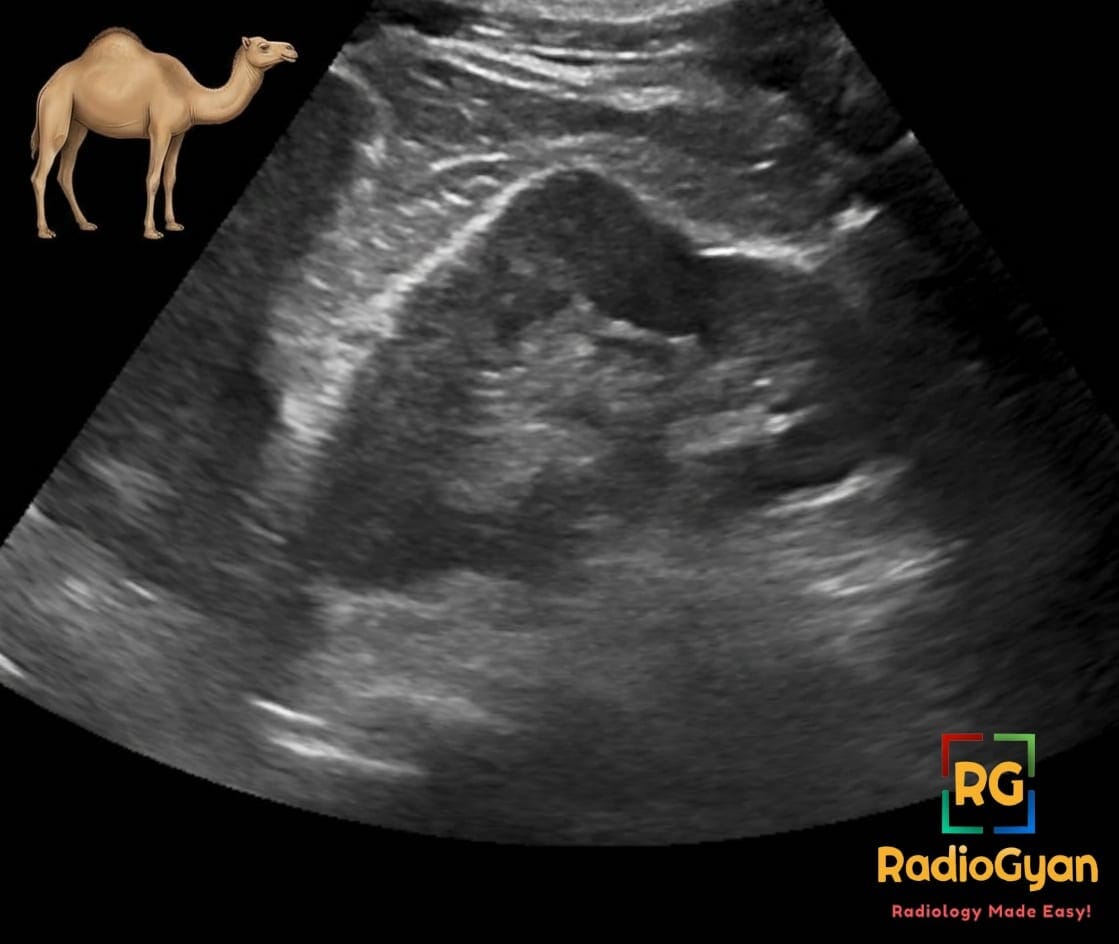

Paracolic Spaces

The paracolic spaces (gutters) are located lateral to the peritoneal reflections of the left and right sides of the colon. The right paracolic gutter(RPG) is larger than the left and communicates freely with the right subphrenic space. The connection between the left paracolic gutter(LPG) and the left subphrenic space is partially limited by the phrenicocolic ligament. Both the paracolic gutters communicate with the pelvic spaces freely.